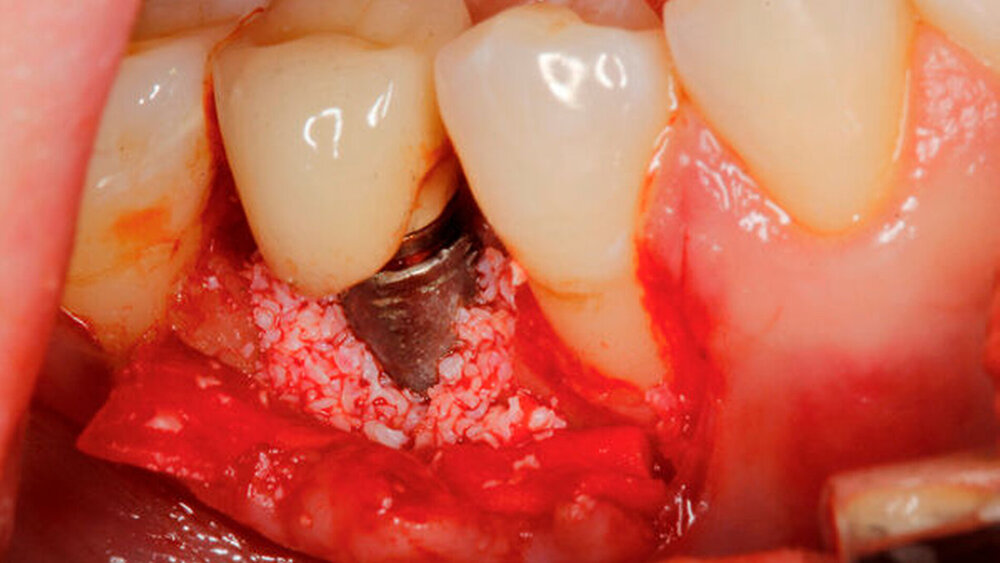

Aktuelle Daten lassen weiterhin keine Rückschlüsse auf die Überlegenheit einer spezifischen Methode zur Implantatoberflächen-Dekontamination [Koo et al., 2018] oder eines chirurgischen Behandlungsprotokolls zu [Khoury et al., 2019] (Abbildung 3). Ein relevanter Einflussfaktor für die Auswahl eines chirurgischen Verfahrens scheint die spezifische Defektsituation sowie die Rauigkeit der Implantatoberfläche zu sein [Monje et al., 2019; Carcuac et al., 2020; Carcuac et al., 2017]. Eine Lappenoperation zeigte bei modifizierten, das heißt rauen, Implantaten eine deutlich geringere Effektivität als bei glatten Oberflächen [Carcuac et al., 2017].

Für augmentative – sogenannte rekonstruktive– Verfahren konnten bisher sehr gute klinische Langzeitergebnisse, insbesondere im Bereich moderat rauer Implantatoberflächen und bei vorliegenden intraossären Defekten, dokumentiert werden [Ramanauskaite et al., 2019; Jepsen et al., 2019] (Abbildung 4a). Bei suprakrestalen Defekten hat sich die sogenannte Implantatplastik in klinischen Langzeituntersuchungen als effektive und sichere Therapieoption bewährt [Stavropoulos et al., 2019] (Abbildung 4b). Bei kombinierten Defekten können rekonstruktive Verfahren mit der Implantatplastik kombiniert werden (Abbildung 4c). Diese kombinierte chirurgische Therapie zeigte in klinischen Studien eine hohe Effektivität über einen bisher dokumentierten Nachuntersuchungszeitraum von sieben Jahren [Schwarz et al., 2017; de Tapia et al., 2019] (Abbildung 5).